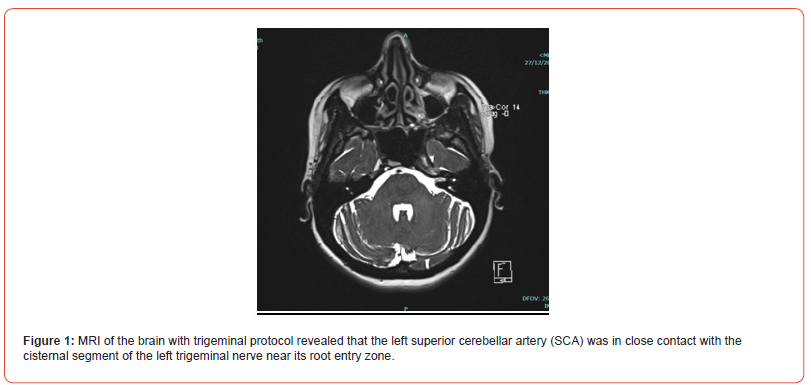

A 44-year-old woman with a history of hypertension and a chief complaint of left-sided facial pain in the V2 and V3 distributions, which had been ongoing for 4 months. MRI of the brain with trigeminal protocol revealed that the left Superior Cerebellar Artery (SCA) was in close contact with the cisternal segment of the left trigeminal nerve near its root entry zone, indicating a potential cause for trigeminal neuralgia. She underwent Microvascular Decompression (MVD) surgery, a common procedure used to relieve trigeminal neuralgia by separating the offending vascular structures from the trigeminal nerve, which led to resolution of her facial pain. However, during follow-up, the patient developed grade 1 facial paralysis, which suggests a complication related to the surgical intervention. (Figure 1 & 2)